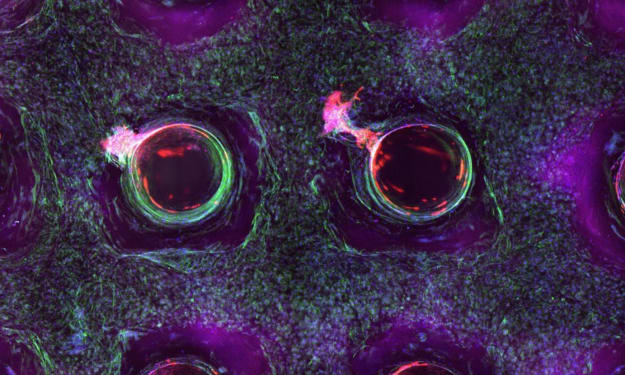

Do our skin have these ???

Title: The Integumentary System: Unveiling the Marvels of Skin, Hair, and Nails Introduction Step into any store, and you'll encounter a vast array of soaps, lotions, conditioners, and polishes dedicated to grooming our skin, hair, and nails. While some view these products as mere vanities, they are, in fact, the tools that care for, maintain, and decorate our integumentary system. Beyond their cosmetic applications, these resilient tissues serve a multitude of functions, many of which go unnoticed. However, when we do notice the workings of our integumentary system, it is often due to uncomfortable or unsightly conditions. This article aims to shed light on the vital functions of our integumentary system, emphasizing the importance of its care and maintenance for overall health.

What about SKIN ?

Title: The Remarkable Complexity of Your Skin: A Closer Look at the Body's Largest Organ Introduction When we think of organs, we often imagine the heart, liver, or lungs. However, we tend to overlook the largest organ of all—our skin. Beyond its external appearance, the skin serves crucial functions, such as protection, temperature regulation, fluid balance, and even vitamin D synthesis. Composed of three layers—the epidermis, dermis, and hypodermis—each with its own unique set of cells, the skin is a remarkable organ that deserves recognition and understanding.